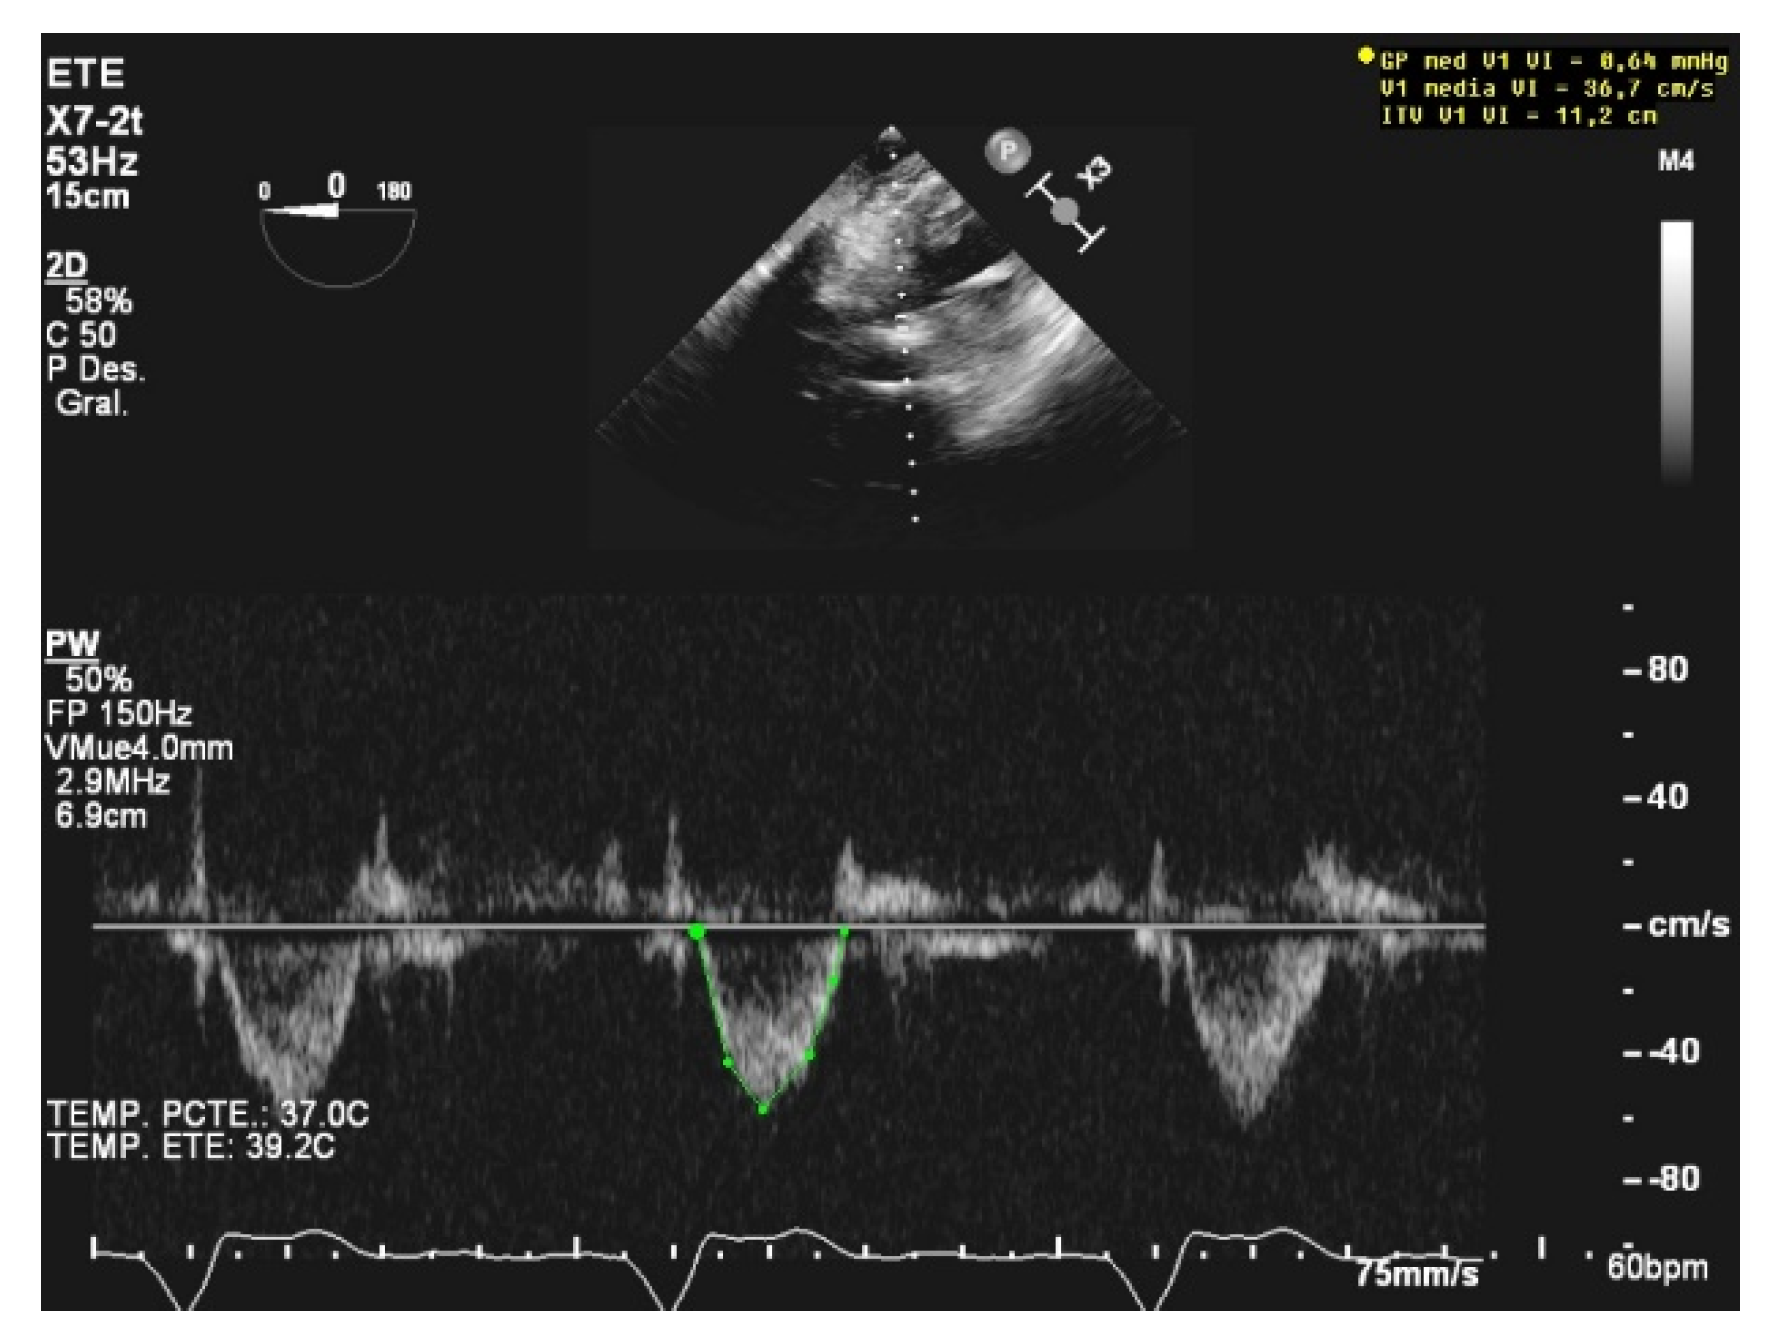

Unlike MV weaning assessment, evaluation of systolic function is the key factor in the decision to wean from ECMO. Weaning can be attempted when the ejection fraction of the left ventricle is higher than 35% and/or the left-ventricular outflow tract velocity time integral (VTI) is higher than 15 cm/s, with a minimal ECMO flow under 1.5 L/min or less than 1500 rpm [9]. Previous studies have also proposed lower values of both ejection fraction (around 20–25%) and VTI (10 cm/s) for a successful weaning [32,33] (Figure 3 and Figure 4).

Figure 4.

Pathological low left-ventricular outflow tract velocity integral (VTI).

Echocardiographic assessment has a limited role in Impella-assisted patients because of the difficulty in measuring the common Doppler parameters due to the noise generated by the device and its placement at the left-ventricle outflow tract [38]. Nevertheless, readiness to wean can be assessed as a function of some imaging features such as a left-ventricular ejection fraction higher than 25%, an aortic velocity time integral higher than 12 cm/s, or a lateral mitral annulus velocity superior to 6 cm/s [39] (Figure 5).